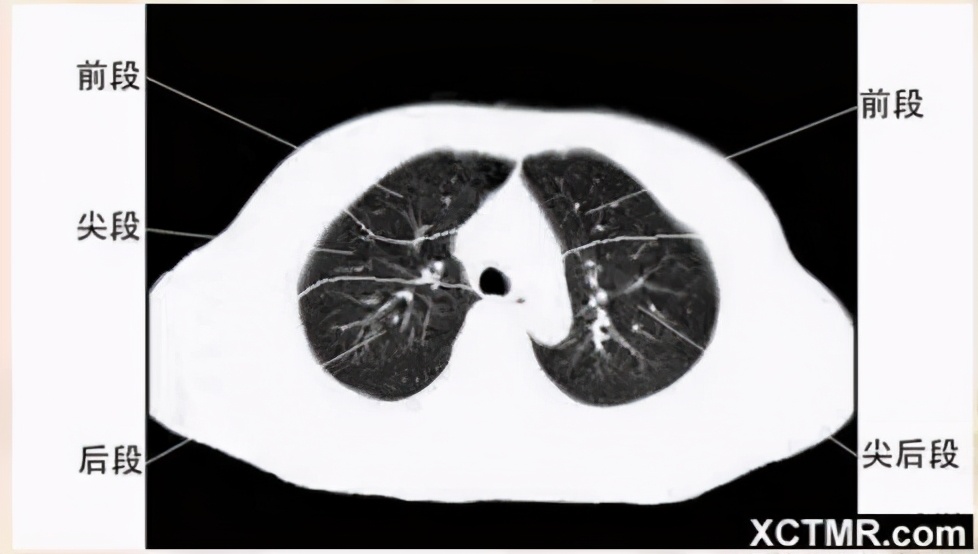

肺段划分